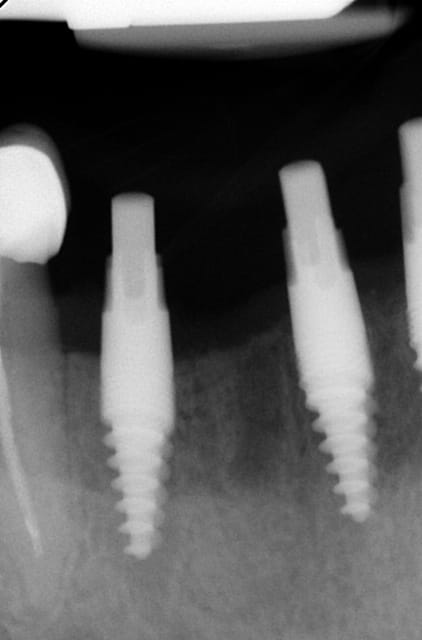

De l'intérêt de garder une dent en secteur 2 ?

Il y a des proximités pour le moins surprenantes .

Des absences d'implants dans certaines zones également .

J'en reviens au premièrement , tu ne mets des implants qu'après extraction , donc on t'enverra des patients avec les dents ...

Ned3 r0bjii - Eugenol